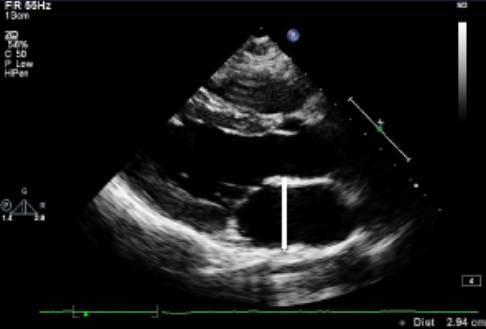

测量位置:胸骨旁左心室长轴,或二尖瓣瓣尖水平左心室短轴切面。

测量内容:室间隔厚度、左心室后壁厚度、左心室内径。

测量时相:收缩末期、舒张末期。

直接二维测量或在二维引导下的M-型曲线上测量。

图|胸骨旁左心长轴切面,二尖瓣瓣尖水平。左图为舒张末期,右图为收缩末期。

随着图像处理技术的改进,已经提高心脏结构的分辨率。可按照真实的组织和血流的界面来测量室间隔和左心室后壁的厚度,而不是像以前测量前缘回声之间的距离。